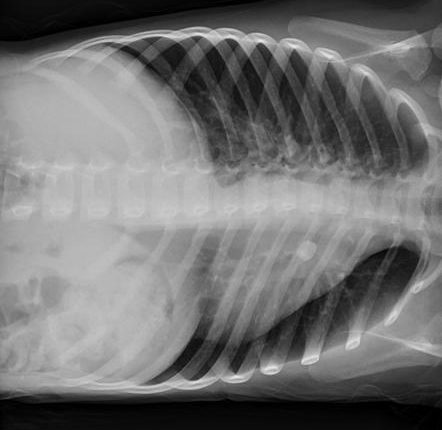

ହରିୟାଣା ରୋହତକ୍ ସ୍ଥିତ ପିଜିଆଇ ହସ୍ପିଟାଲରେ ଡାକ୍ତରମାନେ ଏକ ବିରଳ ଓ କଷ୍ଟସାଧ୍ୟ ଅସ୍ତ୍ରୋପଚାର କରି ଜଣେ ଯୁବକଙ୍କୁ ଛାତିରେ ପଶି ରହିଥିବା ୪୦ ଫୁଟ ଲମ୍ବର ଦୁଇଟି ଲୁହା ରଡ୍ ବାହାର କରିପାରିଛନ୍ତି । ଅପରେସନ୍ ପ୍ରକ୍ରିୟା ଦୀର୍ଘ ୫ ଘଣ୍ଟା ଧରି ଚାଲିଥିଲା । ସୋନିପତ୍ ଜିଲ୍ଲାର କରନ୍ ନାମକ ଜଣେ ଯୁବକ ମାର୍କେଟକୁ ବାଇକ୍ ଯୋଗେ ଯାଉଥିବାବେଳେ ସମ୍ମୁଖରେ ଯାଉଥିବା ଏକ ଲୁହାରଡ୍ ବୋଝେଇ ଟ୍ରକ୍ ସହ ଧକ୍କା ହୋଇଥିଲେ । ଫଳରେ ୪୦ ଫୁଟର ୨ଟି ରଡ୍ ତାଙ୍କ ଛାତିରେ ଫୁଟି ଭେଦ କରିଯାଇଥିଲା । ଗୁରୁତର ଅବସ୍ଥାରେ ତାଙ୍କୁ ପିଜିଆଇକୁ ଅଣାଯାଇଥିଲା । ଡାକ୍ତରମାନେ ପ୍ରଥମେ କଟର ସାହାଯ୍ୟରେ ରଡର ବାହାର ଅଂଶକୁ କାଟିବା ପରେ ଛାତି ଭିତରେ ରହିଥିବା ବାକି ରଡର ଅଂଶକୁ ଅପରେସନ୍ କରି ବାହାର କରିଥିଲେ । ଛାତିରୁ ୧୦ ଇଂଚର ରଡ ବାହାରିଥିଲା । ଅପରେସନ୍ ପରେ ଯୁବକ ଜଣକ ବିପଦ ମୁକ୍ତ ଥିବା ଡାକ୍ତର କହିଛନ୍ତି ।